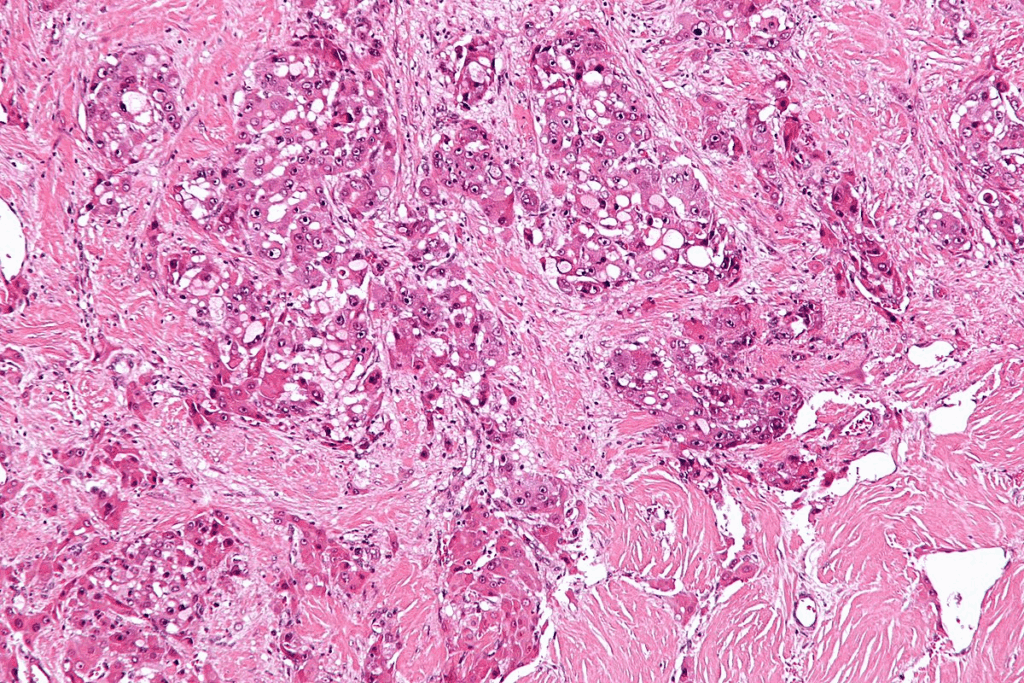

To understand CIS bladder cancer, we must look at its cell features and molecular markers. Carcinoma in situ (CIS) is a serious, non-invasive bladder cancer. It hasn’t broken through the basement membrane yet. Knowing about its pathology helps in early detection and treatment.

Histological Features

The features of CIS are key for its diagnosis. CIS shows marked nuclear enlargement, hyperchromasia, and loss of cellular polarity in the urothelium. These abnormal cells stay in the epithelial layer and haven’t invaded deeper tissues. The urothelium looks disordered or chaotic, with cells showing a lot of pleomorphism.

Looking at the cells under a microscope is vital to tell CIS apart from other bladder issues. The diagnosis of CIS relies on these specific cell features.